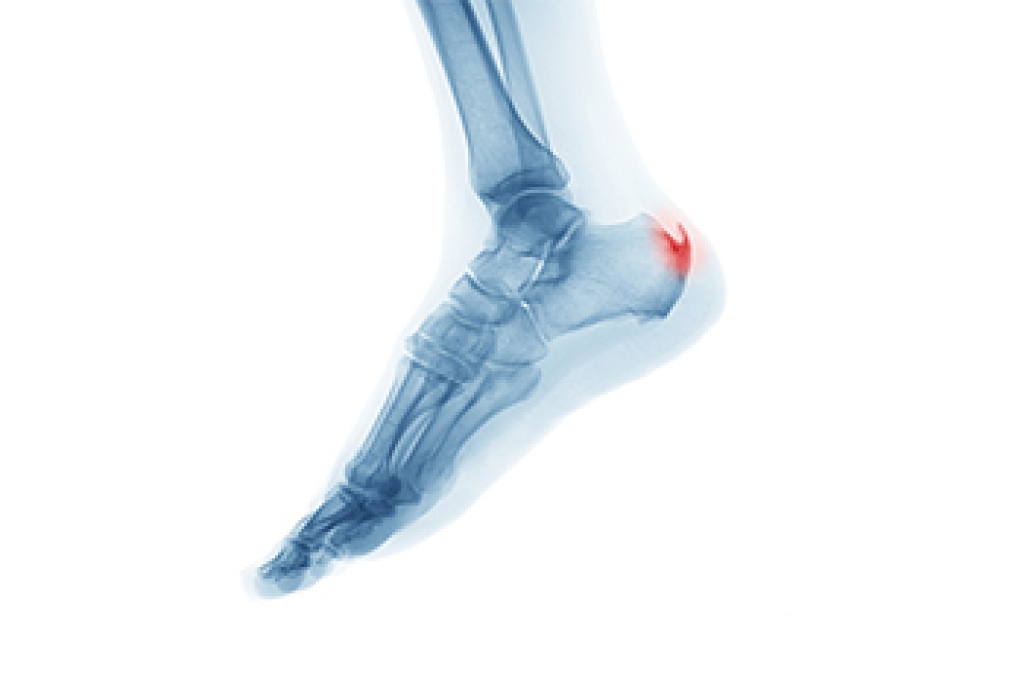

In order to diagnose your bunion, your podiatrist may ask about your medical history, symptoms, and general health. Your doctor might also order an x-ray to take a closer look at your feet. Nonsurgical treatment options include orthotics, padding, icing, changes in footwear, and medication. If nonsurgical treatments don’t alleviate your bunion pain, surgery may be necessary.